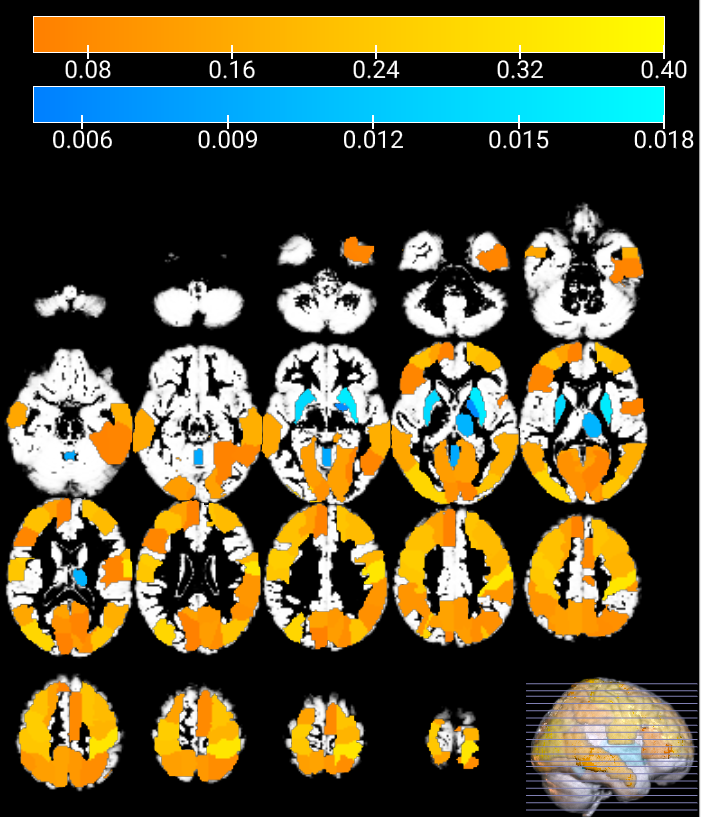

Refer to caption

(a) HC vs ASC permutations comparison of each center with SAM

(b) HC vs HC permutations comparison of each center with SAM

Figure 4: Estimated probability of detection through permutation testing using the SAM mapping method. Each colormap rectangle represents one of the 116 brain regions defined in Table 2 of [57]. The color map depicts the probability of detection of significant differences observed in the regions during the permutation test.

The permutation test, along with SAM, is performed individually for each center in both comparisons (see figure 4 where we display “probability of detection”). Analyzing the results shown in the aforementioned figure, it is possible to distinguish three different sets of centers that show similar behaviour: (i) Firstly, there are centers where no significant differences are observed in any region, regardless of the comparison being made. While this outcome may be anticipated, as it suggests that no specific brain region distinguishes individuals with ASC from HC, it could be surprising that none of the regions exhibit even minimal differences across multiple brains, even if these differences are attributable to random factors. (ii) Secondly, there are centers where the HC vs HC comparison yields no significant differences in any region, similar to the previous case. However, in the HC vs ASC comparison, almost all regions demonstrated significant differences, with remarkably similar frequencies. This is an exceptionally unusual scenario, as it is highly unlikely for all brain regions to exhibit such consistent and significant differences. (iii) Lastly, the centers NYU, UM_1, and YALE exhibit more expected results. In both comparisons, these centers show a mixture of regions with significant differences and regions without significant differences. Overall, these findings highlight the variability in results across centers, with some centers showing no significant differences (conservative behavior of the test), others displaying abnormal patterns of significant differences (nuisance effects), and a few demonstrating more “typical outcomes” with a mix of significant and non-significant regions in both comparisons.

Figure 4 provides a summarized visualization of the probability of detection PDsubscript𝑃𝐷P_{D} of significant differences observed in each center, represented by a color map. After eliminating the defective scans, certain centers show a lack of significant differences across all brain regions (falling into the first case described earlier). Conversely, centers exhibiting a constant PDsubscript𝑃𝐷P_{D} across different regions belong to the second case discussed previously. Among the centers, the NYU center stands out as its results align more closely with the expected outcomes and are similar to those obtained when studying patients according to their condition. It is worth noting that some specific centers display high PD𝑃𝐷PD, i.e. >>0.05 in almost all regions. The high frequency of significant differences observed corresponds to very limited sample sizes, with sizes smaller than 17 scans, in relation to the ’magical’ number proposed in [19].